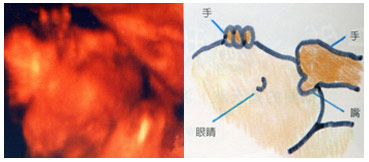

怀孕26周

怀孕26周

胎儿的手正好放在头上,似乎正在思考着事情。